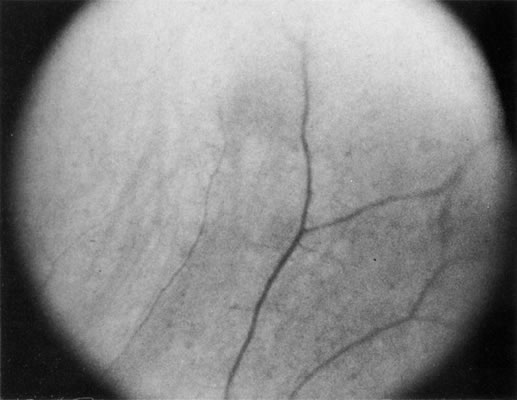

Some retinal dystrophies and degenerative processes can simulate a retinochoroiditis. Vitreous cells may occur in cases of retinitis pigmentosa. Pigmented paravenous retinochoroidal atrophy has a distinctive pattern of pigmentary deposits surrounding retinal veins; it may occur as an idiopathic degenerative disorder or sometimes as a sequela of ocular sarcoid. Fundus flavimaculatus is a rare autosomal recessive dystrophy that is usually detected in the third decade of life. It produces typical comma-shaped, yellowish retinal pigment epithelial opacities in the posterior pole, but it does not involve the macula. It can simulate a diffuse choroiditis (Fig. 24). Myopic degeneration can produce small, white, posterior pole spots that can simulate a posterior choroiditis. Peripheral fundus “paving stone” degeneration is rarely confused with an inflammatory process. These lesions show no evidence of retinal or vitreal inflammation and are quite common.54

Fig. 24. Fundus flavimaculatus. Note comma- or fish-shaped yellowish Figures at the level of pigment epithelium.